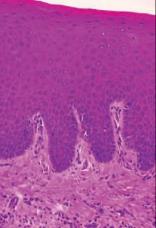

A lichen oris szövettani képe. Az orális lichen szövettani képe sokban hasonló a bőrelváltozás szövettani képéhez, amelyre a subepithelialis, bandázs-szerű, főleg CD8+ T-lymphocyákból álló infiltráció jellemző, azonban szájnyálkahártya-elváltozásban macrophagok is jelen vannak, és a hámban megnő a Langerhans-sejtek száma. Az orális lichen szövettani képére (11.9. ábra11.10. ábra) a következő jellemző: hyperorto- vagy hyperparakeratosis, acanthosis (ami a stratum spinosum sejtjeinek megnövekedett száma miatt alakul ki, majd a basalis sejtek szaporodása miatt a hám a kötőszövetbe kesztyűujjszerűen hatol be), valamint a bandage-szerű kereksejtes beszűrődés a kötőszövetbe. A bazális membrán területén és a bazális sejtekben hidropikus degeneráció néha a hám- és kötőszövet szeparációjaként manifesztálódik, és vezet a bullózus forma kialakulásához. Többször egyéb elváltozások, mint pl. az atrophia is látható. A reticularis lichenben is felfedezhető hámszövet-degeneráció. A nem erozív lichen szöveti képére jellemző a fokális epithelialis sejtelhalás következtében kialakuló üres sejtek (angolul civatte bodies), amely a programozott sejthalál, az apoptózis jelensége. Az apoptotikus sejteket a macrophagok távolítják el. Citoid „civatte” testek azonban nem betegségspecifikus struktúrák, immunglobulinokat és komplement komponenseket tartalmaznak. Ezek magas előfordulása jelzés, de nem diagnosztikus értékű. A kötőszövetben vaskos, bandage-szerű lymphocytabeszűrődés észlelhető. Azonban egyértelmű, hogy a T-lymphocyták megjelenése nem az epithelialis sejtpusztulás következménye, hanem annak okozója. A lichen oris direkt immunfluoreszcens (DIF) vizsgálatának eredménye magasan specifikus. Drága, de néha szükséges vizsgálat. A bazális membrán zónában fluoreszkáló csík látható, de csak nagyon ritkán ad pozitív reakciót anti-IgA, anti-IgG vagy antiIgM ellenanyaggal. Nincs immunglobulin depozitum. Sokkal gyakrabban lehet kimutatni fibrinogénlerakódást a basalis membrán alatt, amely antifibrinogén ellenanyaggal kimutatható. Ez azonban más autoimun betegségben is kimutatható. A betegség patogenezise még nem egyértelműen tisztázott, de valószínű, hogy valamilyen antigén hatására kialakuló immunválasz jön létre a szájnyálkahártya hámjában, ami a domináns T-sejtes infiltrátumot is megmagyarázza.

11.9. ábra. Acanthosis, a stratum spinosum sejtjeinek számának megnövekedése

11.10. ábra. A lichen szövettani képe, bandage-szerű kereksejtes beszűrődés